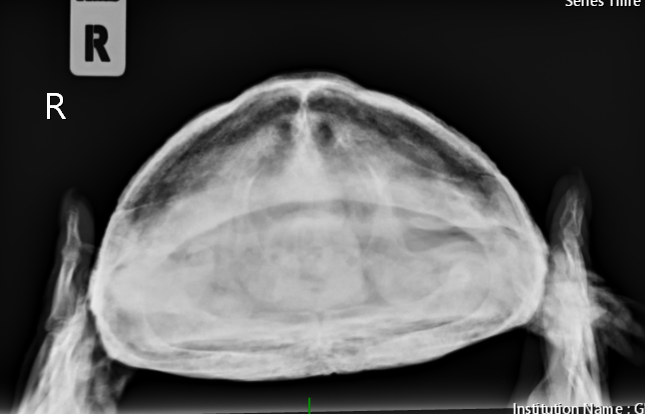

Консультанты moth Ваше имя: Мария Локация: Москва Опубликовано: 7 сентября 2023 Консультанты Опубликовано: 7 сентября 2023 @Алёна.Е. Вам всё в ту же клинику с ней нужно - делать рентген лапы и смотреть что с костями. Если там внутри всё сгнило, то только ампутация. Если нет, то можно пробовать антибиотики. Вы ещё не записывались на приём? Рыбу она поела?

Консультанты moth Ваше имя: Мария Локация: Москва Опубликовано: 8 сентября 2023 Консультанты Опубликовано: 8 сентября 2023 @Алёна.Е. врач ответила, что нужно обязательно рентген. Мускусные черепахи склонны к "гниению" конечностей и скорее всего там гнойный артрит и некроз + сверху бактериальный дерматит. рыбу конечно предлагайте.

Алёна.Е. Ваше имя: Алёна Локация: Пермь Опубликовано: 13 сентября 2023 Автор Опубликовано: 13 сентября 2023 Здравствуйте, были на приёме в клинике 11.09. Рентген сделали, назначили антибиотик, ванны с бетадином и прослушивание. От рыбы также отказывается. Если поможет то лапку попробуем спасти. Фаланги уже рыхлые до локтя. Есть вероятность опухоли, но гисталогию не делали ещё.

Консультанты moth Ваше имя: Мария Локация: Москва Опубликовано: 13 сентября 2023 Консультанты Опубликовано: 13 сентября 2023 @Алёна.Е. а снимков нет на руках? я бы нашему врачу показала, спросить её мнение. Попробуйте предложить улиток, мидий или креветку (желательно сырую) без панциря